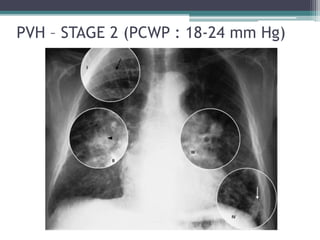

Stage 2 PVH

• PCWP : 18 – 24 mm Hg

• Interstitial edema

• Kerley B lines

• Peribronchial cuffing

PVH – STAGE 2 (PCWP : 18-24 mm Hg)

Stage 2 PVH •PCWP : 18 – 24 mm Hg • Interstitial edema • Kerley B lines • Peribronchial cuffing

PVH – STAGE2 (PCWP : 18-24 mm Hg)